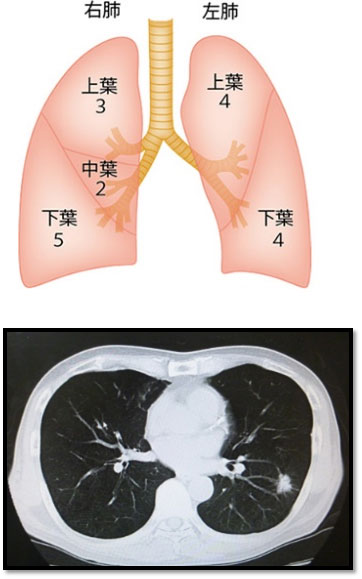

左図のように、肺は左右に5つの袋からなり、これを肺葉と呼びます。右図に描かれている数字は大きさを相対評価しています。中葉が最も小さく、下葉が最も大きくなります。肺がんの多くは検診(健診)の胸部レントゲン検査で発見され、精密検査として胸部CT検査(右図)が行われます。CTでは左右が逆となって写りますので、白い影(腫瘍)は左肺に存在していることになります。ここで初めて、“肺がんの疑い”となります。